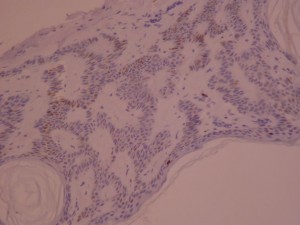

Ki-67 staining of an acantho-hyperkeratotic type of SK. On the last picture, most of the basal staining comes from the accumulation of pigment as the clinical image suggests.

Ki-67 staining of an acantho-hyperkeratotic type of SK. On the last picture, most of the basal staining comes from the accumulation of pigment as the clinical image suggests.

Ki-67 staining of an acantho-hyperkeratotic type of SK. On the last histological picture, most of the basal staining comes from the accumulation of pigment as the clinical image suggests.